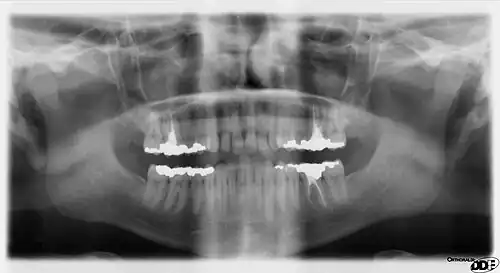

Rarely, a bifid IAN may be present, resulting in a second and more inferiorly placed mandibular foramen. This can be detected by noting a doubled mandibular canal via radiograph.[10]